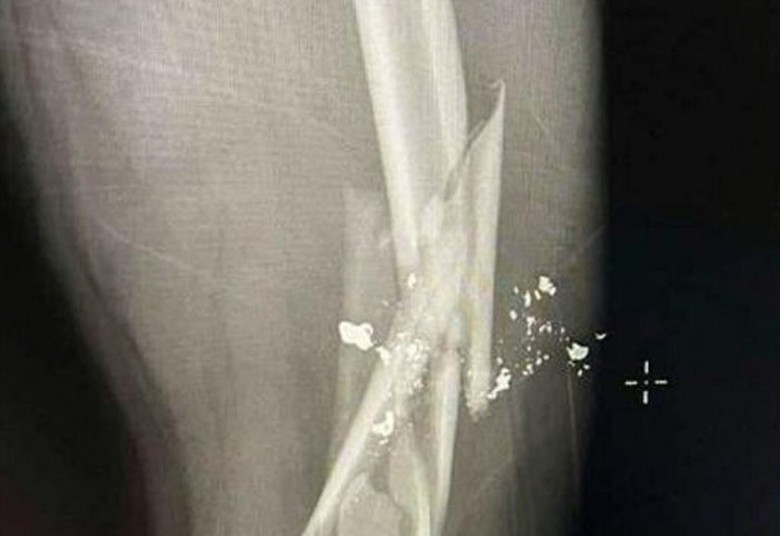

Hình ảnh xương đùi anh G. bị gãy (Ảnh Vietnamnet)

Trong quá trình ăn nhậu, giữa H. và anh G. xảy ra mâu thuẫn và xô xát. Sau đó, H. đã lấy súng bắn gãy đùi anh G.